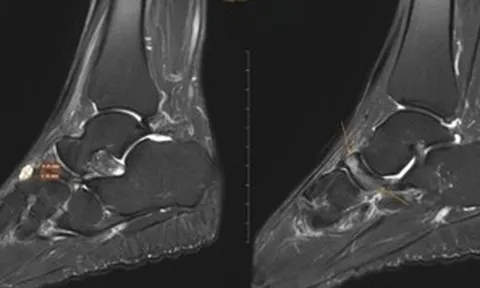

Ngay sau đó, các bác sĩ đã nhanh chóng tiến hành chụp cắt lớp vi tính bụng, tiểu khung, lồng ngực, sọ não và thực hiện các xét nghiệm cận lâm sàng, hội chẩn các chuyên khoa Cấp cứu, Hồi sức tích cực – chống độc, Khoa Ngoại nhi.

Kết quả chẩn đoán cho thấy, trẻ bị suy hô hấp độ 3, sốc chấn thương, đa chấn thương. Bé gái còn bị chấn thương ngực kín, gãy xương sườn bên trái, đụng dập nhu mô, tràn khí – tràn máu màng phổi hai bên, chấn thương bụng kín, chấn thương gan độ 3, chấn thương lách độ 3.